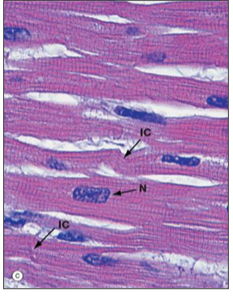

what type of muscle is depicted in this longitudinal section

Cardiac muscle

Identify the labeled image

G – gap junction

F – fascia adherens

D - desmosome

What is depicted in the image

Intercalated discs